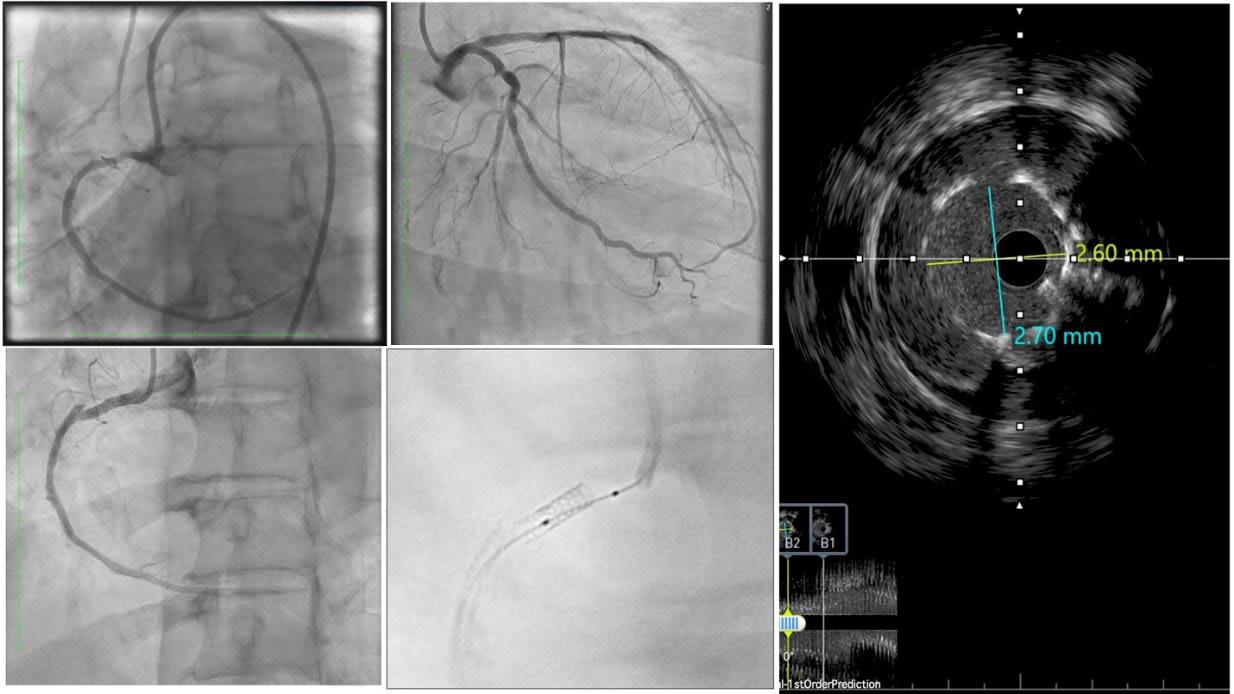

do a similar analysis in Europe, it's probably 80% receiving alcohol ablation, and if you go to Asia, the percentage undergoing alcohol ablations is even higher. In general, I think there has been a larger adoption of minimally invasive procedures in Europe and Asia, partly for spiritual reasons in Asia, and in Europe, I think it’s more due to lack of availability of surgical centres. Whereas, in the USA, there are many large centres that have shepherded hypertrophic cardiomyopathy care for many, many decades, and so surgery continued on as a primary modality. I do think that in the appropriate hands, the mortality rate is better and the efficacy is similar with alcohol ablation (in the appropriate patients), and so the only detriment really is the pacemaker rate. Mostly, patients over the age of 50 or 60 years typically don't mind this, because if they get a pacemaker at that age, it's usually not too much of a burden. It also allows monitoring of the patient for atrial fibrillation or other arrhythmias that might prevent sudden cardiac arrest down the line.

The problem with both of these procedures is that they are very hard to teach and, like any other procedure, you need to do a certain number of them to maintain the credibility and expertise over time. So, in the 2011 American Heart Association (AHA) guidelines, we recommended that institutions should do 10 procedures a year to maintain certification, credibility, and expertise, but very few places can do that. In our heyday, we were doing about 40 alcohol ablations and 30 myectomies a year here. Now, with the use of mavacamten and other cardiac myosin inhibitors, the volume of procedures done will be cut in half. So, one of the main challenges is,

how do you set up major centres to offer this? With this in mind, we developed a course. It's over 10 years old now; we had a break during the COVID-19 pandemic, but we've done roughly seven courses since its inception, and they have been very popular. The only way to learn this procedure is to see a few of them at once. We usually have about three cases over the course of 2 days, and then, through didactics, we discuss all of the alcohol ablation details, including preprocedural and intraprocedural planning and post-procedure management. We then take attendees through live cases, where we go through the procedure step-by-step on actual patients. Finally, we end with critical care rounds, where we look at the patients afterwards and discuss their ECG, pacemaker requirements, and how to manage them before they go home. It's a very comprehensive course and we’ve probably trained over 100 people who have all gone out to do the procedure. So, it does work and now they have the experience. Even if they don't do 10 per year, they have a network of individuals who they can run cases by and refresh their ideas on the tools and the equipment needed, and how to plan for that procedure for that given patient.

I do think that surgeons should do the same thing. They have not developed a course in this space. I have advised that they do because I think that both these procedures are very important and valuable for the population, including in Europe. About 10 years ago. Barry Maron wrote a paper entitled, ‘Bring Septal Myectomy Back for European Patients’,1 which was essentially a call to action, highlighting that we do need capable surgeons out there to do this. I would be an advocate for that as well.

In the surgery field, they train in their fellowships, but then afterwards there's not a whole lot of training opportunities, from what I can see. I think it's more in the mindset of interventional cardiology to proctor other people and spread these procedures more broadly. But I think within the surgical field, they tend to rely on their societies and their training pipeline, and not necessarily courses like these. Additionally, they tend not to train their competition. Now, you can say the same thing for interventional cardiology, but I specifically bucked that trend by saying: “I'm going to train people to compete with me.” That’s because the greater good is more important. I know it's easy to say that, but the truth is that in any field, people tend to hold on to their trade secrets. Now, with that being said, I will say that our surgeons were trained by the Mayo Clinic surgeons, but that was through a personal relationship. Though I think the Mayo Clinic surgeons have done a good job of going out and training individual surgeons at other institutions, and I give them credit for that, I do wish that somebody would take the mantle and develop an actual course. We did think about expanding our course to include surgeons, but again, it depends on funding and the availability of surgeons who are willing to do it.

Q3 Can you tell us about your book, ‘Lindsay's Big Heart’. How does improving patient/family health literacy correlate with treatment adherence and outcomes in the HCM population?

I'm a creative person; I like doing different things and coming up with new ideas. This idea came out of a desire to spread HCM awareness a lot broader, and

books have a way of spanning globally. In other words, they can be translated to other communities. And actually, we've had some interest from the HCM Foundation in Europe, as well and other places, to translate the book.

The reason for spreading awareness for HCM is that most patients with HCM seek medical attention when they are middleaged, which means that they have probably been living with their HCM for decades. It's known to start in puberty and teenage years, so there's usually a long latency period where they have the disease but no symptoms. We would like to catch people at that stage where they're developing hypertrophy but don't have symptoms, so we can start getting them treated earlier and possibly prevent progression.

The second issue is that a lot of these people have kids, and they have no idea how to talk to their kids about this disease. I feel like if a woman has breast cancer, they sit their daughter down, tell them about breast cancer, and why they need to have mammographies. However, we don't do the same for other genetic diseases, like HCM, and because of that, I wanted to have a tool that parents can read to their kids while they're young, before the HCM even develops, if it even develops. That way,

when they get older and their ECG looks suspicious or they have symptoms, they will not be scared to tell their doctor that there is HCM in their family. At the moment, I do not see that happening, and the only way to get that to happen is to educate people at an age where they can see that this is running in their family and not be scared of it. That's the second part of it, which is something the book really addresses: how to digest this disease as one thing in your family and not be scared of it.

We would like to catch people at that stage where they're developing hypertrophy but don't have symptoms

What you see is a young girl go through this and lead a very happy, normal life. It shows that none of the testing was scary, and she can go on to do all the things she wants to do; she just happens to have this bigger community of physicians, parents, and other people who now know her and how to protect her, including having defibrillators in the school and people around her knowing CPR. So, I think the

book comes out of this genuine idea to have a resource for kids where they can be curious and understand their disease in a way that makes sense to them.

At the same time, we didn't want to water the information down. We made sure that the book has pictures that are accurate, and every picture included has educational value, including having defibrillators visible and showing the different testing that people get throughout their evaluation and management. I spent a lot of time on additional pages for parents at the end: two pages on how to keep your kids safe, and two pages that define all the complicated medical terms that even parents wouldn't understand, so that they're prepared when they go into their doctor's appointment. So, there's a little bit of a dictionary at the end to help people understand the top 20 words that come up in this disease. I wanted to make sure the book really spanned both parents and kids.

If we have the energy and funding, we would like to translate the book into different European languages, certainly Spanish and French, and then eventually Mandarin and Arabic. I'm not sure what else, but those probably cover a large portion of the world. HCM is a disease that spans both genders and all races, and happens

in rich communities and poor communities; I do want to get it to all kids of the world. A 19 USD book is something that you can get everywhere, including for free in libraries, whereas actual healthcare is not quite as egalitarian.

Are you planning on writing any other books?

I’m not writing any at the moment, because I have a lot on my plate right now, but the publisher that we have has already mentioned that they would love to have more of a series. Lindsay Davis is one of my friends with HCM and this book is modelled after when she was around 8 years old, and Kiran, the boy in it, is my son, and it's modelled after when he was also 8 years old. He's sort of the ‘smarty pants’ kid who teaches her a lot whilst in the hospital after having a false alarm. So, I think one of the ideas was to have a Lindsay and Kiran series, where they can each be the protagonist, depending on the disease state. For example, the next book could be about Kiran's peanut allergy. There's so much opportunity to talk about something like that and make different conditions and diseases less scary.

Q4Your work on the 2019/2022 universal cardiogenic shock definitions revolutionised trial design. How have these criteria impacted mortality stratification in recent studies like RECOVER III?